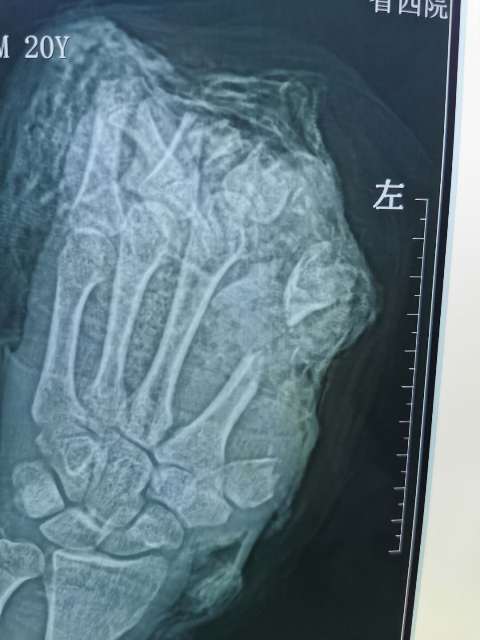

10月6日,20岁的小伙在工厂干活时左手不慎被切割机致左手拇指、示、中、环指完全离断;左小指开放伤伴肌腱神经血管离断;大鱼际皮肤软组织、环指中末节部分缺损、第一掌骨、第二掌骨部分缺损,鲜血直流。被工友慕名紧急送往21点策略指南站

经过骨二科和手术室医务人员历时10小时,彻底清除污染失活组织及伤口内大量铁屑异物、逐步固定指骨、缝合肌腱,显微下再次清创后吻合离断神经;术中见离断动脉大部分挫伤严重无法吻合就近利用手背侧静脉,移植搭桥吻合缺损动脉完成4指离断一期急诊再植,术后经补液输血,支持,抗感染,抗凝,抗痉挛,扩血管等“三抗一扩”对症治疗。目前患者再植指体成活良好,已经基本度过危险期,保住了患者的四个手指。